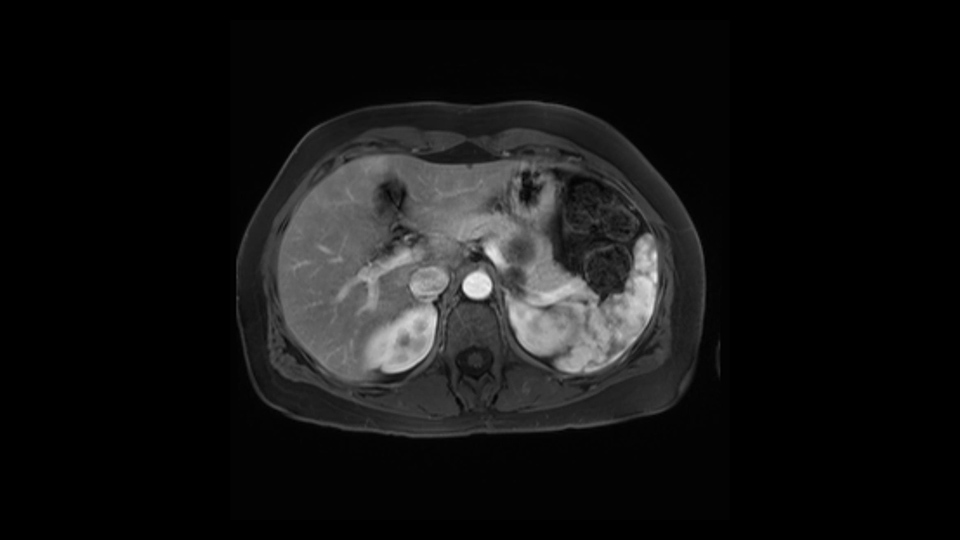

So first, I'll show you the scan. Here's the traditional view, where you see the cyst, which is in the body of the pancreas. And you see over here, it's got a quite thick wall. And going a little bit back also, here you see a septation which is very important, because I think a septation is what separates this from, for instance, the pseudocyst of the pancreatitis. And also the location of the cyst you see here, abutting the adrenal gland and going down a bit more, it's also quite close to a bowel loop. So when thinking about this cyst: female, the location in the body of the pancreas, thick wall, septation, and as you can read in history, it was basically asymptomatic, so no signs of pancreatitis. So, this probably all points towards a mucinous cystic neoplasm.

In reviewing this patient’s CT scan, first of all, the lesion is again cystic with a very thin wall. I anticipate that it will be delicate and potentially friable. And therefore the risk of rupture exists and we need to be very careful in how we handle the pancreas and the tumor throughout the procedure.

The lesion itself is quite adjacent to and abuts the splenic vein and therefore we need to anticipate that these two structures will be intimately related and possibly impossible to separate between the two.

The lesion also is quite posterior. While the plane between the cyst and the left adrenal gland is often preserved, we do have to pay attention here so that we remain in the right plane and maintain our margin here. Occasionally in these cases, en bloc adrenalectomy needs to be performed.